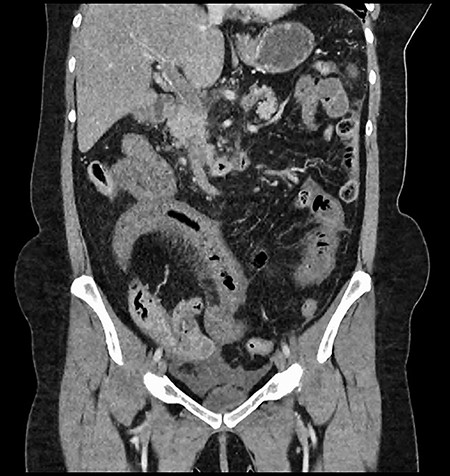

A 61-year-old female presented to a regional hospital with a 3-week history of intermittent diarrhoea, vomiting and generalized abdominal pain. She had a diffusely tender abdomen but was not peritonitic, and was shocked with a heart rate of 110 beats per minute, blood pressure of 89/45 mmHg and was peripherally cool. Her blood tests revealed a lactate of 7.2 mmol/L, which worsened to 7.8 mmol/L during resuscitation with intravenous fluids, and white cell count was 30.9 × 109/L, with an international normalized ratio (INR) of 1.4. She had an acute kidney injury with a creatinine of 119μmol/L and estimated glomerular filtration rate (eGFR) of 43 mL/min/1.73m2. Computed tomography (CT) revealed extensive thickened loops of non-enhancing small bowel with pneumatosis, moderate free fluid and a large splenic infarction. There was extensive thrombosis of the splenic vein and superior mesenteric vein extending into the portal vein to the level of the porta hepatis. Her background history included factor V Leiden and protein S deficiency, for which she had been non-compliant with warfarin during this illness. She had no surgical history (Figs. 1–5).

CT showing complete occlusion of the portal vein at the level of the porta hepatis.